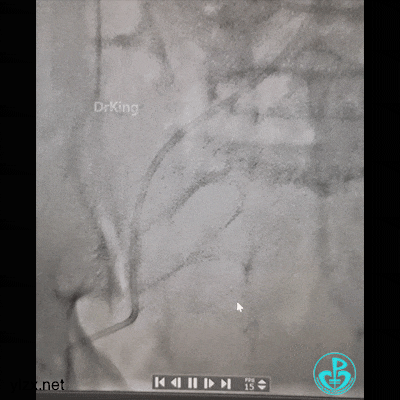

现在时间充裕,解决腿上打折的管子。

J-W软头端无法通过管子。

换硬头端(铤而走险、不常规推荐)。

管子头还是打不开,调整一下。

打折处通了,换软头端(直头端不敢出GC)。

管子头段直啦。

拉出来了。

股A造影正常,撤台,安返CCU。